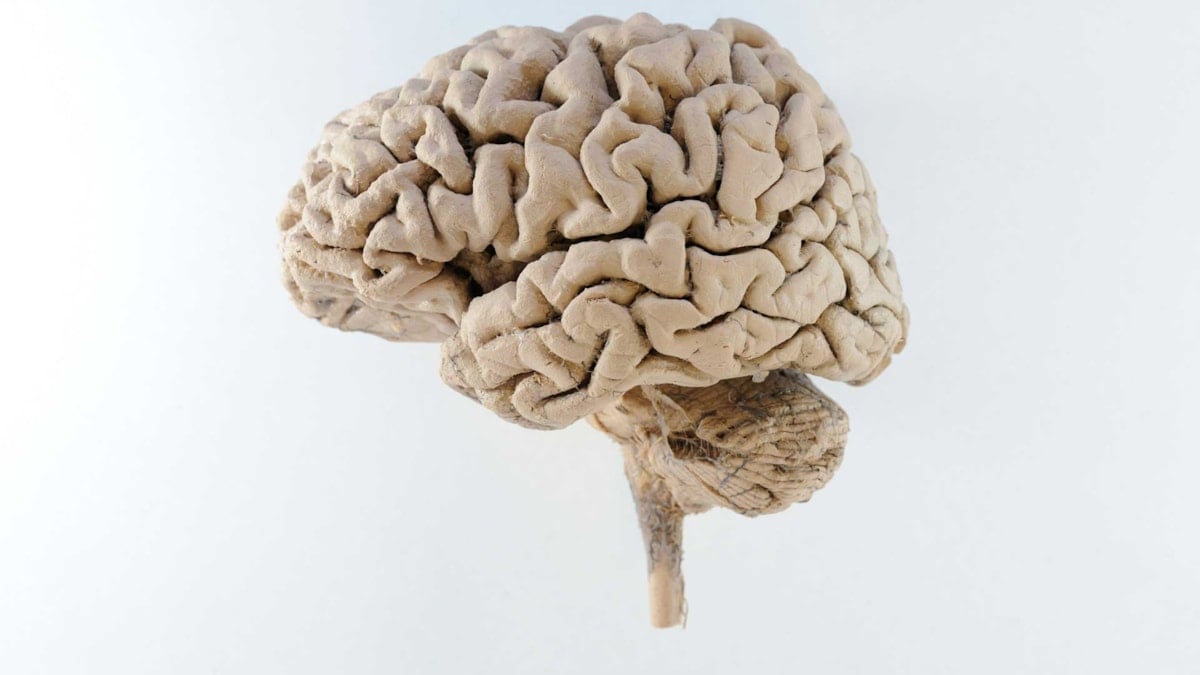

Om hjernen

Hjernekartet

Vi har laget et digitalt hjernekart, som viser deg hvordan det ser ut inne i hjernen og hvordan hjernen fungerer. Og hva som skjer når det oppstår en skade i hjernen.